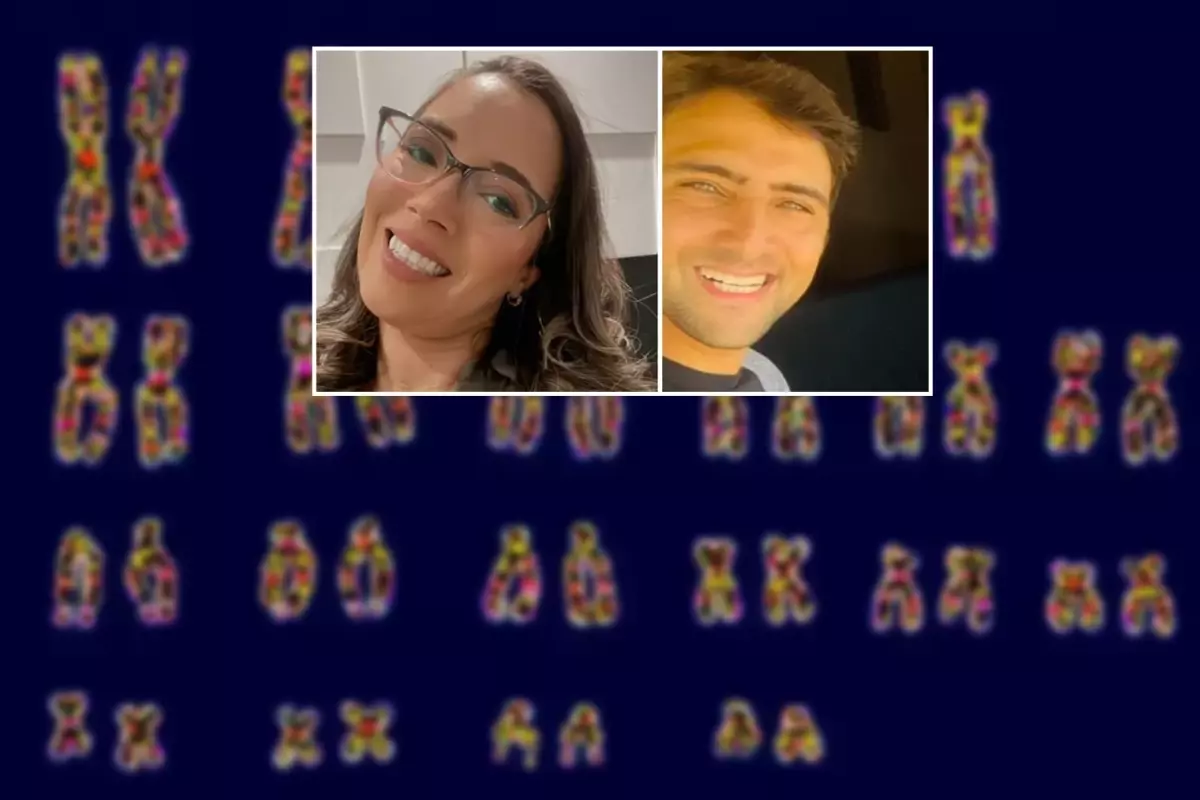

Ana Paula Martins isimli kadının vücudunda kadınların cinsel özellikleriyle ilişkili XX kromozomu hem de erkeğe ait XY kromozomu tespit edildi. Tıp dünyasında ilk kez görülen bu vaka doktorları bile şaşkına çevirdi. Paula'nın XY kromozomlarının anne karnındayken ikiz erkek kardeşinden geçtiği düşünürken doktorlar, "Yani erkek kardeşinden bir parça içinde dolaşıyor" diyerek durumu özetledi.

Ana Paula Martins'in vücudundaki her hücrede kadınların cinsel özellikleriyle ilişkili XX kromozomları bulunuyor. Ancak kan hücrelerinde erkeğe ait XY kromozomları da tespit edildi. Tıp dünyasında ilk kez görülen bu vakada doktorlar, Ana Paula'nın kanındaki XY kromozomlarının, anne karnındayken ikiz erkek kardeşinden geçtiğini düşünüyor. Bu keşif, Ana Paula'nın 2022 yılında düşük yapmasının ardından yapılan araştırmalar sırasında ortaya çıktı.

Jinekoloğun önerisiyle yapılan karyotip testi, Ana Paula'nın kanında XY kromozomlarının bulunduğunu gösterdi. Sonuçlar hem doktorları hem de Ana Paula'yı şaşkına çevirdi. Fleury Medicina e Saude'de görev yapan ve São Paulo Üniversitesi Tıp Fakültesi'nde profesör olan jinekolog Gustavo Maciel, "Hastayı muayene ettim. Tamamen normal kadın özelliklerine sahipti. Rahmi, yumurtalıkları vardı ve yumurtalıkları aktifti" dedi. Daha sonra Ana Paula, Albert Einstein İsrail Hastanesi'nde genetik uzmanı Dr. Caio Quaio'ya yönlendirildi.

Araştırma sırasında Ana Paula, ikiz kardeşinin olduğunu açıkladı. Yapılan DNA karşılaştırması, yalnızca kan hücrelerinin ikiz kardeşiyle aynı olduğunu ortaya koydu. Prof. Maciel, "Ağzındaki DNA'da, tenindeki DNA'da o kendisi. Ama kanında kardeşi var" diyerek durumu özetledi. Doktor Quaio, "Yani erkek kardeşinden bir parça içinde dolaşıyor" dedi.

İnsanlarda cinsiyet kromozomları da dahil olmak üzere 23 çift kromozom var (XX veya XY)

İnsanlarda cinsiyet kromozomları da dahil olmak üzere 23 çift kromozom var (XX veya XY)